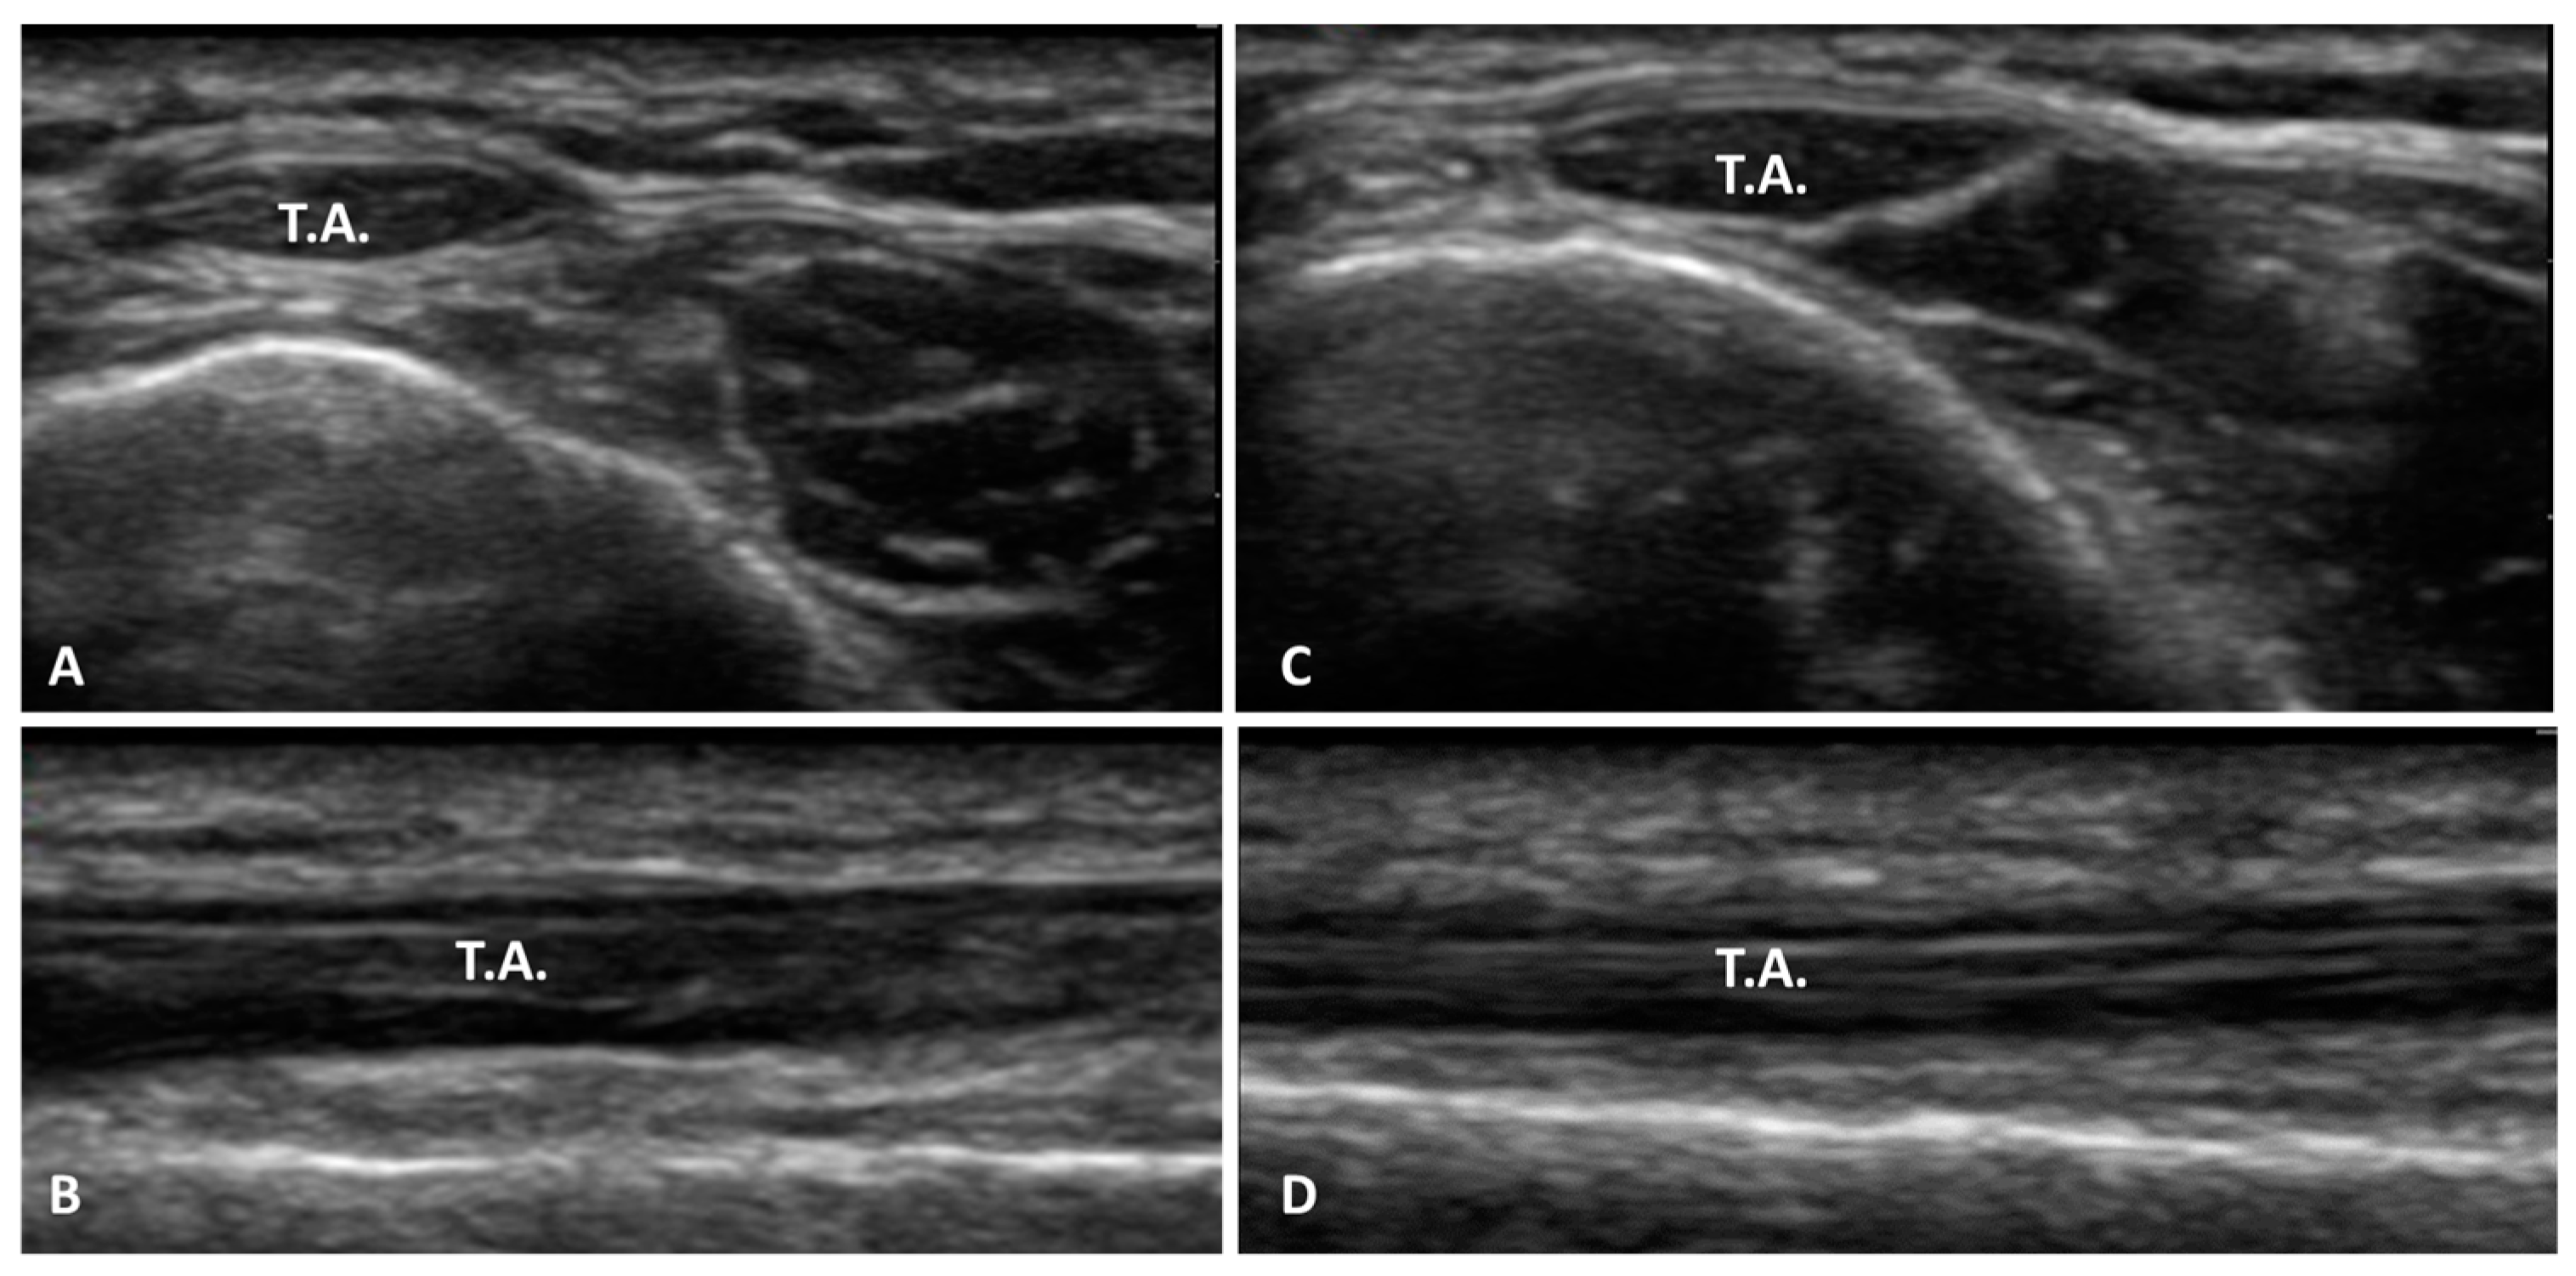

3.1. Ultrasound Measurements of the Superior Extensor Ankle Retinaculum

3.1.1. Group 1 (Football Players with Previous Multiple Ankle Sprains)

3.1.2. Group 2 (Healthy Volunteers)

3.6. Echogenicity Measurements